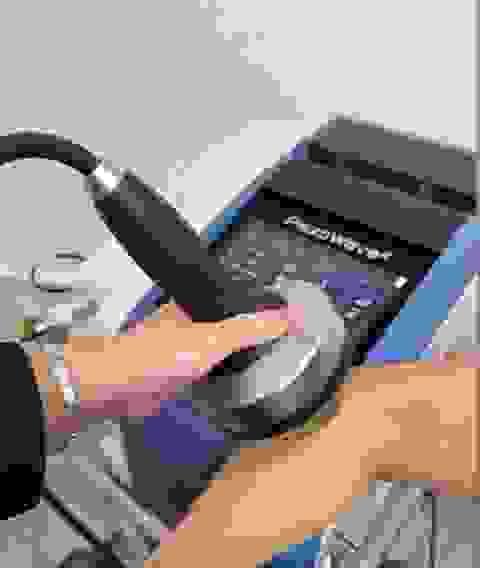

Shockwave 衝擊波治療

第二代衝擊波治療 德國頂尖儀器 衝擊波是一種高能量聲波,可於體外穿透皮膚表層進入身體組織而不會刺破皮膚,屬於非入侵性治療,近年常被應用於脊椎治療及肌肉治療上,以治療韌帶、筋腱、韌帶及軟組織等的痛症。 德國品牌:首部應用於治療激發點的聚焦式衝擊波 採用兩層耐用的壓電(Piezo)晶體,能產生強而穩定的震波 不同形狀的治療頭,透入深度可達60mm 治療頭出口寬闊,降低震波能量密度,大大減輕治療時的痛楚 聚焦式衝擊波,有效治療筋腱病變,治癒率高達九成選擇日期與時間